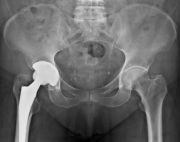

1. Osteoarthritis of both hips but is more severe on the right side.

Treatment: Total hip arthroplasty in a 73-year-old female

I. Anteroposterior x-ray of the pelvis and hips II. One-month post-surgery, anteroposterior x-ray pelvis shows the THA III. One-month post-surgery, lateral x-ray of the right hip showing the exact position of the stem in the femur